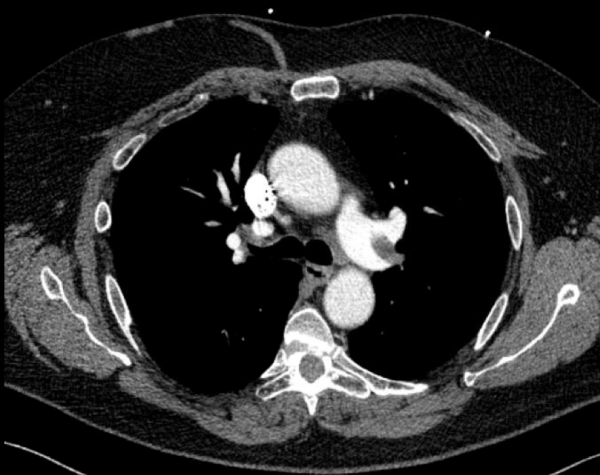

CT angiography of the chest with intravenous contrast was performed.

There is a filling defect straddling the bifurcation of the pulmonary trunk extending into the distal branches of the right lower, right middle, right upper and left upper lobe consistent with a saddle embolism. Bedside echocardiography revealed mild concentric hypertrophy, an ejection fraction of 60%, with normal right ventricular global systolic function, with no evidence for an elevated right ventricular systolic pressure.